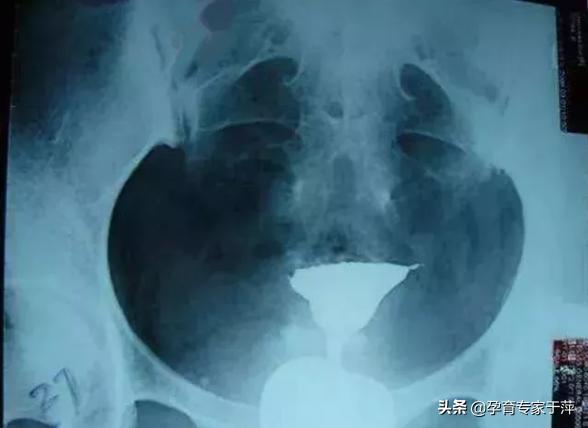

5、输卵管积水

造影片的表现是一侧或双侧输卵管远端增粗、膨大,呈“腊肠状”。这是由于输卵管远端粘连不通导致输卵管内造影剂不能溢出所导致。所以,输卵管积水的前提是输卵管不通。如果造影片显示输卵管伞端有造影剂溢出就不是积水。